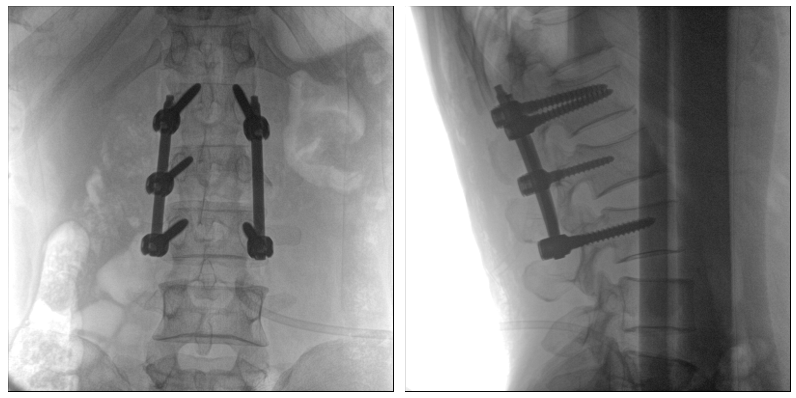

術中二維影像

從圖中可以看到二維影像能夠提供目標區域在某一個平面的重疊影像,雖然因為人體不同組織的密度差異,使得圖像具有較為豐富的信息量,但組織間的相互重疊還是會出現,諸如空間位置等眾多信息在影像中遺失或不可辨認的情況,影響了醫生對信息的收集與應用。